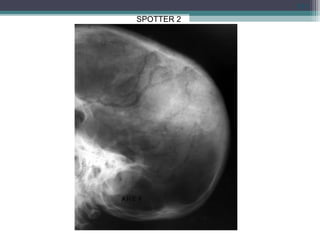

SPOTTER 2

• MENINGIOMA: INCREASED VASCULAR

SUPPLY TO PARTIALLY CALCIFIED MASSS.